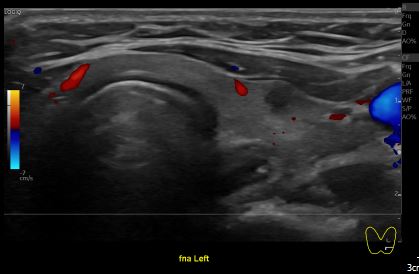

상기환자 갑상성 결절 추적관찰 하시는 분으로 40대중반 여성분으로

의심스러운 갑상선 좌엽 결절 세포검사 진행후 갑상선암으로 진단되었습니다